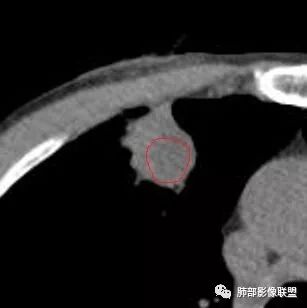

南边:周围晕、细微毛刺都属于炎性特点这一部分单独拿出来类圆形,边缘光滑,按理恶性特征不明显;但是加在一起,转移瘤就不排除总体倾向于炎性,转移瘤不除外

南边:就目前的征象符合炎性,我认为炎性病变一定有但是有部分边缘膨隆,恶性不能排除,等炎性吸收后看看,或穿刺血管纠集南边:

南边:我们担心的,它是在一个转移的基础上,还有合并有炎症,担心这个隐藏在其中,因为它这个边缘,是不是很清楚光滑哈,但是我们都记得转移瘤,他很多都是边界清楚光滑的,对不对。就觉得,中间这个结节跟周围的病灶好像形态、密度各方面都不一致的。我就担心它是一个转移瘤,合并感染,周围炎性病变,中间是一个转移瘤结节这样的就麻烦了。所以常规我会建议他抗炎治疗后复查。看看那个残留的病灶怎么样,本质是如何,要么穿刺,这个病变我只能说炎性它一定有。南边:里面那个病灶就是那个类圆形的病灶,跟外面那个肯定是不一致的,就那个类圆形病灶,到底是一个转移瘤,还是单纯炎性病变的部分。目前这个片只能等复查,毕竟边缘是膨隆的,而且我们刚才也说了,转移瘤的特点,如果血道转移,他就是边界清晰光滑的。所以成这样,有这么巧的话你就没办法。南边:关于血管纠集,它就这样的,炎性病变也可以这样表现,牵拉过来,原理不同,但是影像表现已经表现很类似,我们往往关注支气管。支气管进入这个病灶的表面的时候是否堵塞,或者血管,进入这个病灶里面,是否走行是否自然;这些这些可能价值大一些,但是他是不是一个恶性征象,是;但是它的比例就是在炎性病变也不低。原发呢,不敢说没有,但是一般来说几率偏低吧。

结果:活检病理:右上肺肺泡慢性炎;肺泡腔内纤维素样渗出伴出血。

综上,更支持慢性炎性病灶。隐球菌感染不能排除,无论是影像特点,还是患者不相关的临床表现。